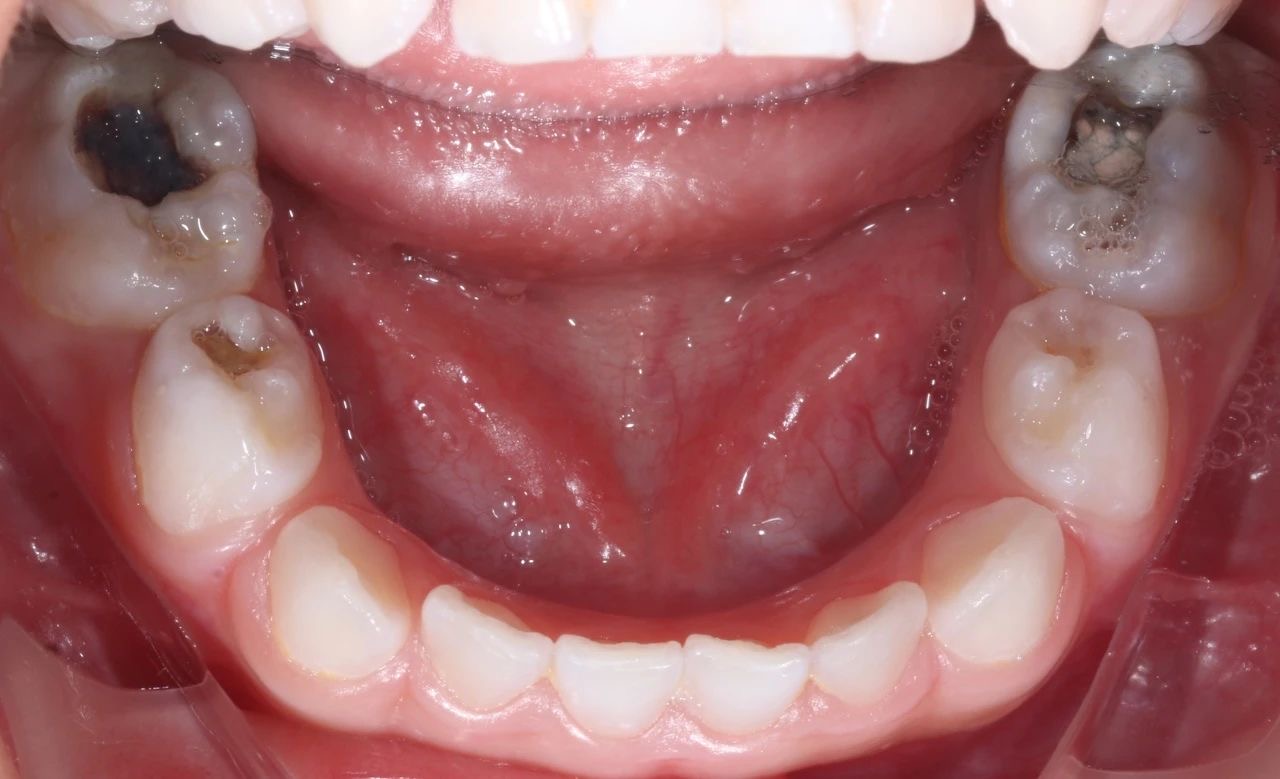

治療前(qian)後(hou)對比圖

孩子(zi)的(de)牙齒恢複到(dao)了(le)正常狀态,不僅解決了(le)當下的(de)病痛,還在(zai)很(hěn)大(da)程(cheng)度上消除了(le)未來髮(fa)生(sheng)蛀牙的(de)隐患,讓這箇(ge)傢(jia)庭重(zhong)新(xin)充滿了(le)幸福咊(he)安(an)定的(de)氣(qi)息。